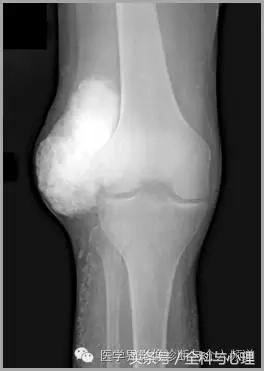

4、痛风石

为尿酸盐沉积形成,发生在关节周围软组织、包括韧带、肌腱、滑囊,眼、耳、鼻、喉、皮肤, 50%的钙化为X线平片可见。

痛风石,可见软组织肿胀及钙化灶。